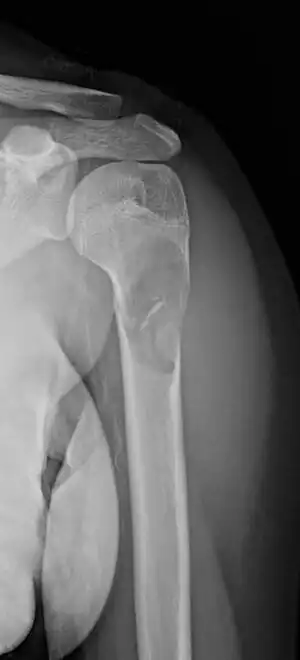

| X-ray: Simple bone cyst in left upper arm of 13 year old | |

A simple bone cyst, also known as a solitary bone cyst, is a non-cancerous cavity in bone, filled with a yellow-colored fluid, usually in a long bone of a child.[1][2] It is usually discovered by chance as often there are no symptoms, but may present with an unexpected broken bone, pain, swelling or reduced movement.[1][2]

Most simple bone cysts do not cause any symptoms and are discovered as accidental findings on radiographs or CT scans made for other reasons.[3] Although it can form in any bone structure, it is predominantly found in the long bone of the upper arm near the shoulder, and long bone of the thigh near the hip.[6] Large lesions can cause nearby areas of bone to thin, which may result in a fracture and cause pain.[1][2] There may be a swelling or problem in moving the affected bone.[1]

Simple bone cysts are often found incidentally on X-rays. About 90 to 95% of the lesion is found in metaphysics of long bones. The cyst is centered, oblong in shape along the long axis of a long bone. Rarely, they are large and multicameral and are found in diaphysis. When fracture is present, there may be a small bone fragment migrated in the cystic fluid. This is called "fallen fragment sign" which is diagnostic of simple bone cyst. Besides, a bubble migrating upwards (known as "rising bubble sign") is another feature suggesting of simple bone cyst.[7]